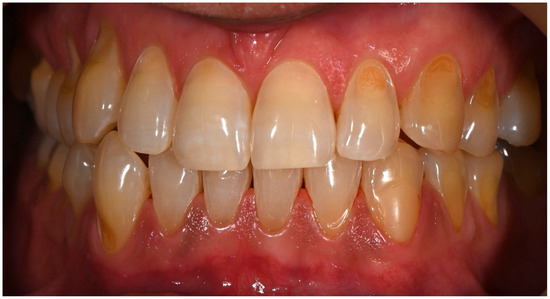

Clinical Management of Cervical Restorations with Closing Gap Technique: A Follow-Up of Two Cases

Background: Cervical restorations remain clinically challenging due to complex anatomy, limited enamel availability, and difficulties in achieving reliable adhesion at dentin or cementum margins. Polymerization shrinkage and marginal leakage are frequent causes of failure. Although the Closing Gap Technique has been proposed to [...] Read more.

Background: Cervical restorations remain clinically challenging due to complex anatomy, limited enamel availability, and difficulties in achieving reliable adhesion at dentin or cementum margins. Polymerization shrinkage and marginal leakage are frequent causes of failure. Although the Closing Gap Technique has been proposed to improve marginal adaptation in cervical restorations, evidence supporting its medium- to long-term clinical performance is limited. The aim of this case report was to evaluate the clinical effectiveness of the Closing Gap Technique in the restoration of carious and non-carious cervical lesions. Materials and Methods: Two patients presenting with cervical lesions were treated using the Closing Gap Technique. One case involved carious cervical lesions, while the second included multiple non-carious cervical lesions. Restorations were performed following an enamel-anchored incremental layering protocol with resin composite. Clinical evaluations were conducted at 8 years (case #1) and 2 years (case #2) post-treatment, respectively. Results: Both cases demonstrated favorable clinical outcomes at follow-up. The restorations exhibited good marginal integrity, satisfactory esthetics, absence of marginal discoloration, no secondary caries, and no signs of debonding. The only minor defect observed was slight chipping of one of the restorations. Conclusions: Within the limitations of this case report, the Closing Gap Technique showed stable and predictable medium- and long-term clinical performance, supporting its use as a viable restorative approach for managing cervical lesions in daily clinical practice. Full article